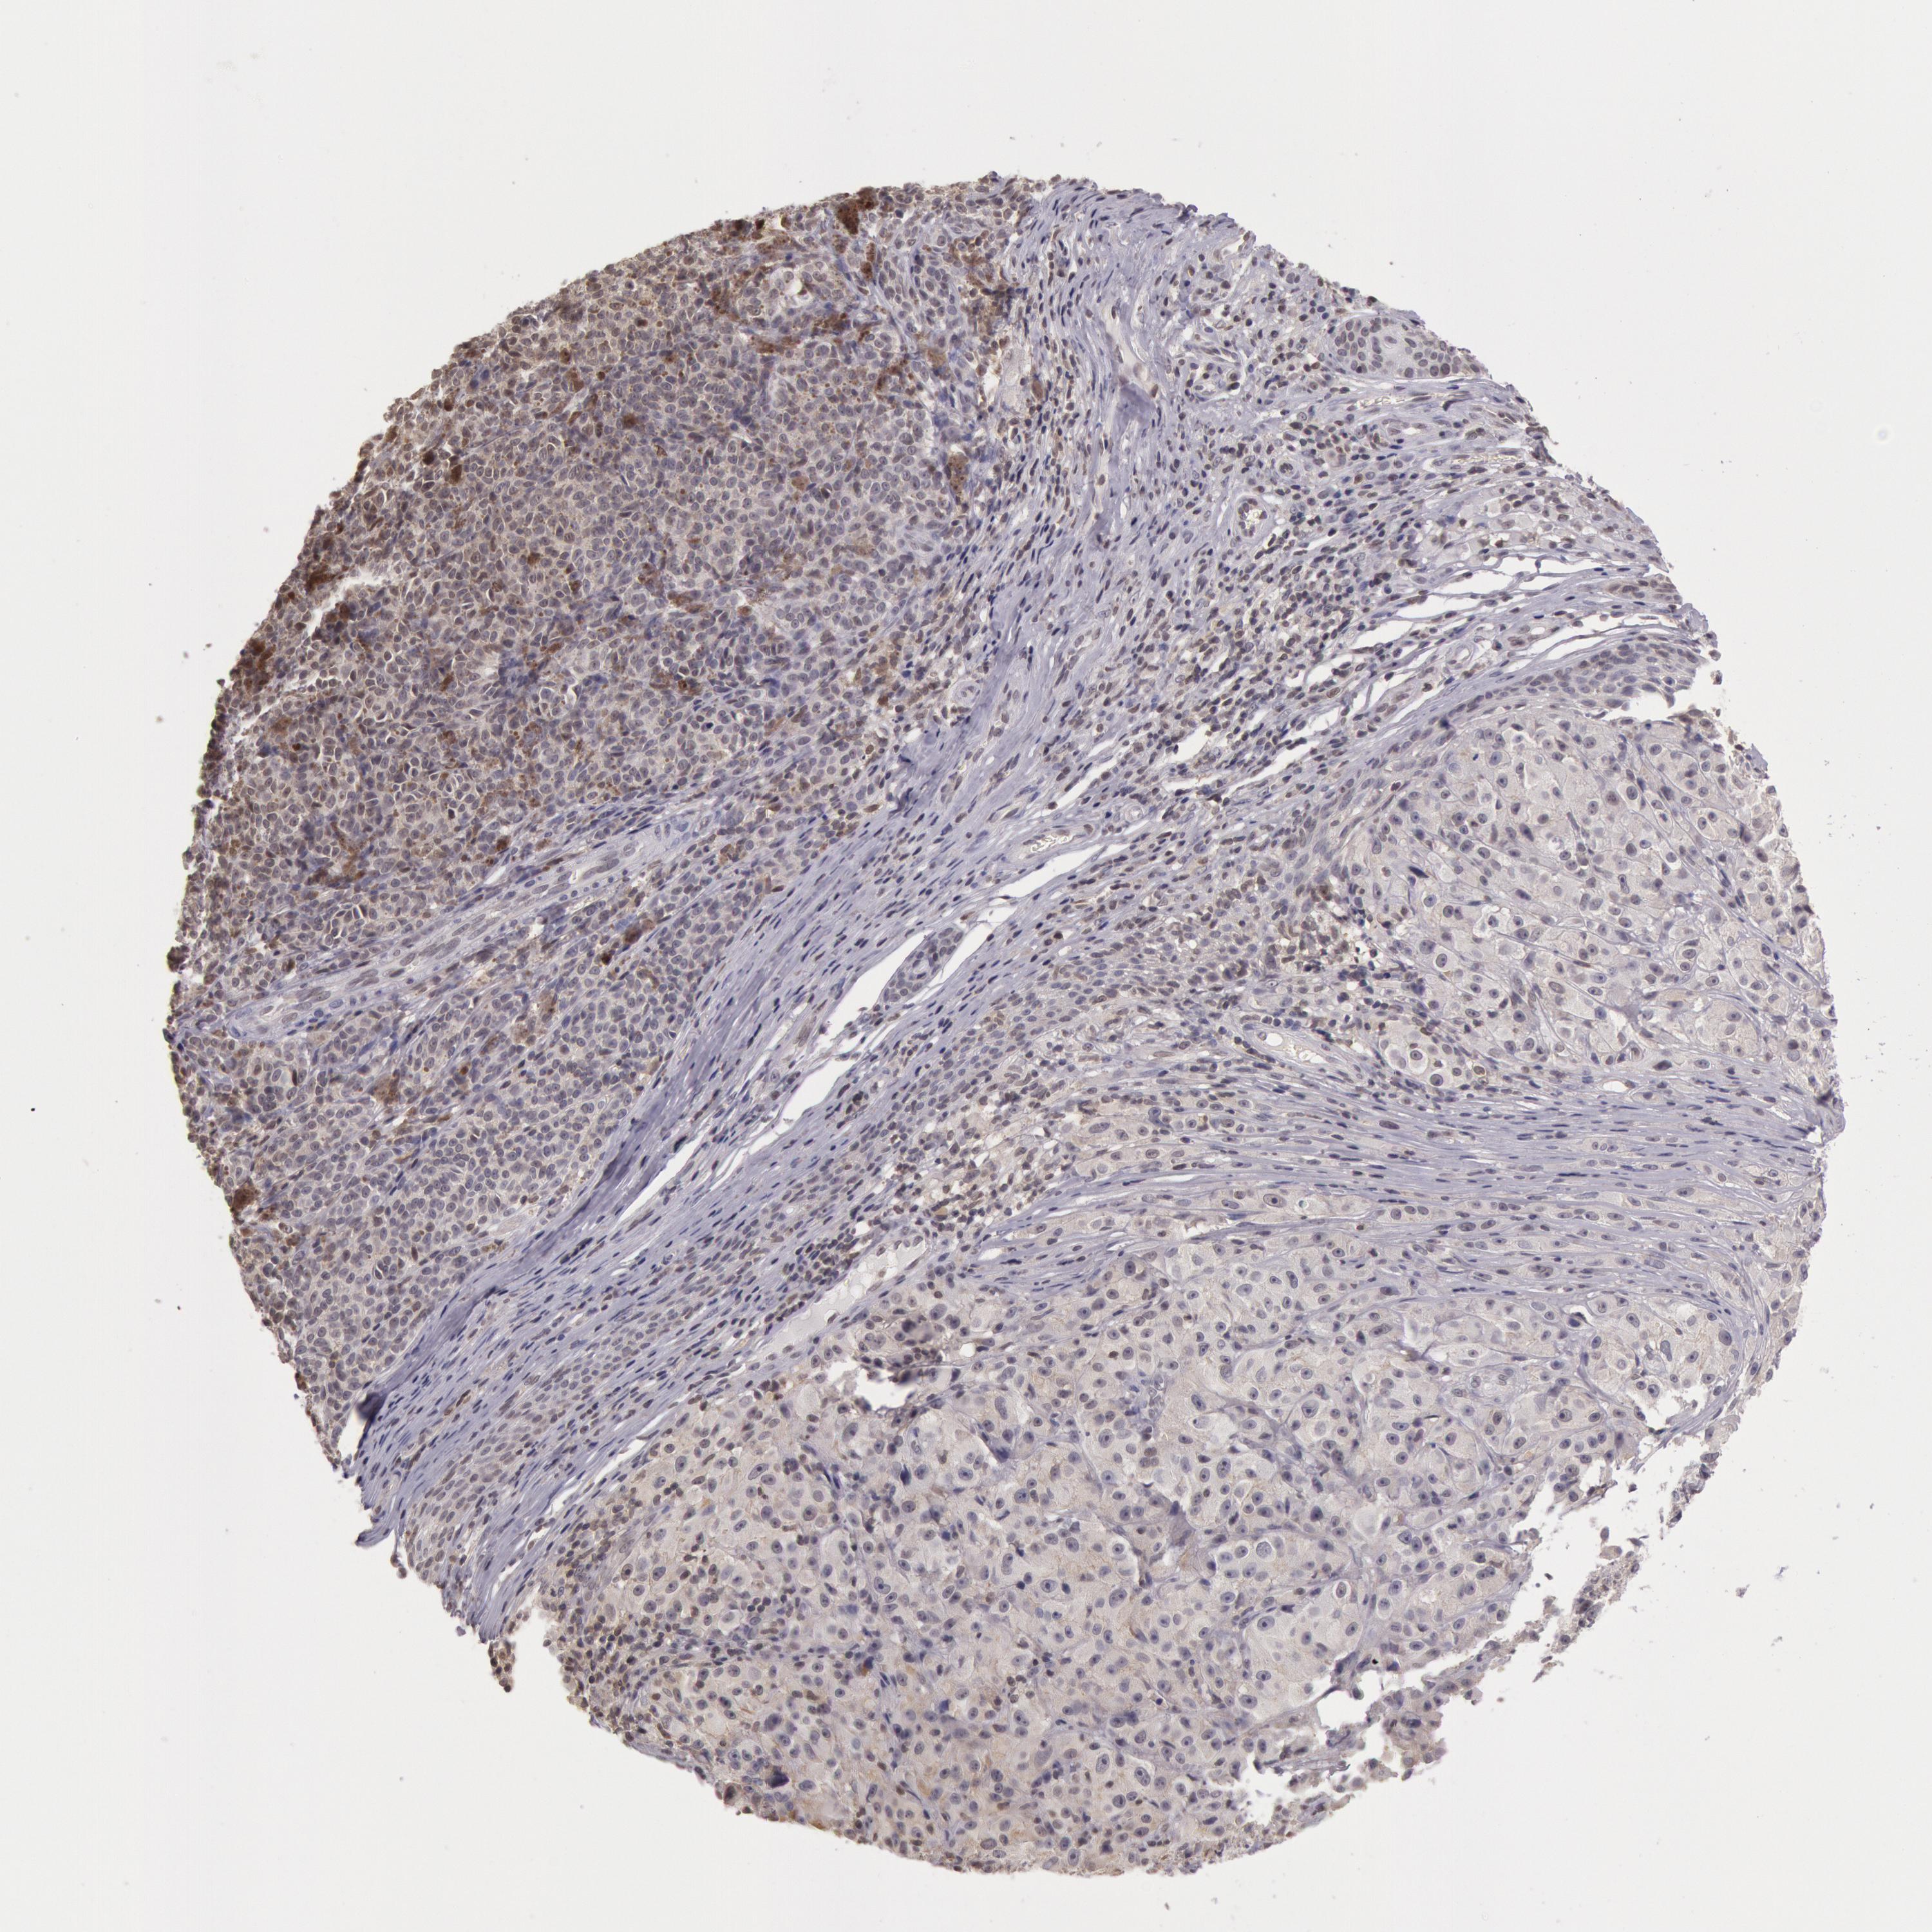

MELANOMA - Protein expressioni

A mouse-over function shows sample information and annotation data. Click on an image to view it in a full screen mode. Samples can be filtered based on level of antibody staining by selecting one or several of the following categories: high, medium, low and not detected. The assay and annotation is described here.

Note that samples used for immunohistochemistry by the Human Protein Atlas do not correspond to samples in the TCGA dataset.

Antibody stainingi

Antibody staining in the annotated cell types in the current human tissue is reported as not detected, low, medium, or high, based on conventional immunohistochemistry profiling in selected tissues. This score is based on the combination of the staining intensity and fraction of stained cells.

Each image is clickable and will lead to virtual microscopy that enables deeper exploration of all samples and also displays staining intensity scores, fraction scores and subcellular localization as well as patient and tissue information for each sample.

Antibody HPA001275

Antibody CAB017442

Staining

High

Medium

Low

Not detected

Intensity

Strong

Moderate

Weak

Negative

Quantity

>75%

75%-25%

<25%

None

Location

Nuclear

Cytoplasmic/membranous

Cytoplasmic/membranous,nuclear

Malignant melanoma, NOS

Malignant melanoma, Metastatic site